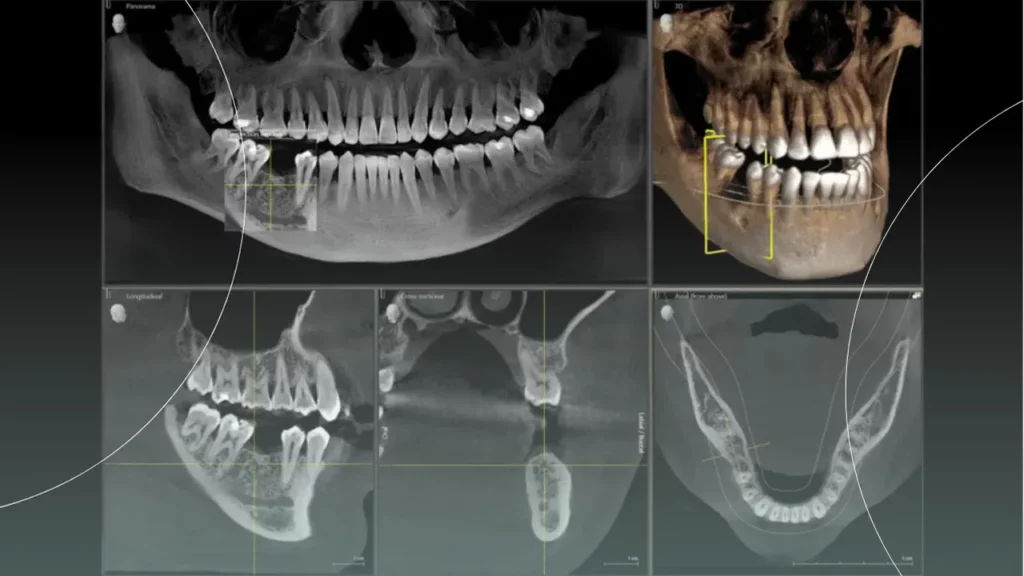

- سی تی اسکن با اشعه مخروطی (CBCT): این یک تکنولوژی پیشرفته است که یک تصویر سه بعدی (3D) از دندان ها و فک ها ارائه می دهد. CBCT فقط در موارد پیچیده مانند دندان های نهفته در موقعیت های دشوار، شکاف کام و لب یا برنامه ریزی برای جراحی های دقیق فک استفاده می شود و یک ابزار روتین برای همه بیماران نیست.

| CBCT | نمای کامل سه بعدی از دندان ها و استخوان فک | موارد بسیار پیچیده، دندان های نهفته دشوار، برنامه ریزی جراحی |